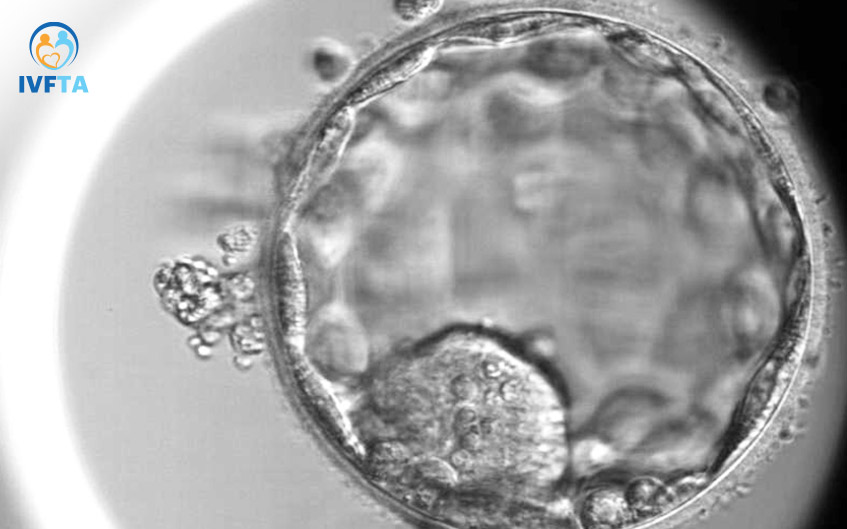

Hiện nay nhằm đảm bảo tỷ lệ thành công và giảm nguy cơ đa thai trong chu kỳ thực hiện thụ tinh trong ống nghiệm IVF, việc nuôi cấy phôi ngày 5 và chọn lọc những phôi có tiềm năng làm tổ cao trở thành yếu tố cốt lõi. Việc nâng cao chất lượng phôi bằng cách nuôi cấy phôi đến giai đoạn phôi ngày 5 (phôi nang) đang là một xu hướng tất yếu trong điều trị hỗ trợ sinh sản.

Phương pháp này dựa trên các yếu tố chỉ những phôi tốt về mặt hình thái, di truyền và khả năng phát triển tốt mới tiến triển lên đến giai đoạn phôi ngày 5. Tỷ lệ phôi làm tổ thành công ở giai đoạn phôi nang lên đến 60-70%.

Sau khi kết hợp tinh trùng với phương pháp IVF cổ điển hoặc ICSI, 16-18 giờ sau các chuyên viên phôi học sẽ kiểm tra sự thụ tinh giữa noãn và tinh trùng. Các noãn thụ tinh thành công sẽ được theo dõi và đánh giá về hình thái của hợp tử, quá trình phân chia của tế bào xuyên suốt quá trình phát triển đặc biệt ở giai đoạn phôi ngày 3, ngày 5.